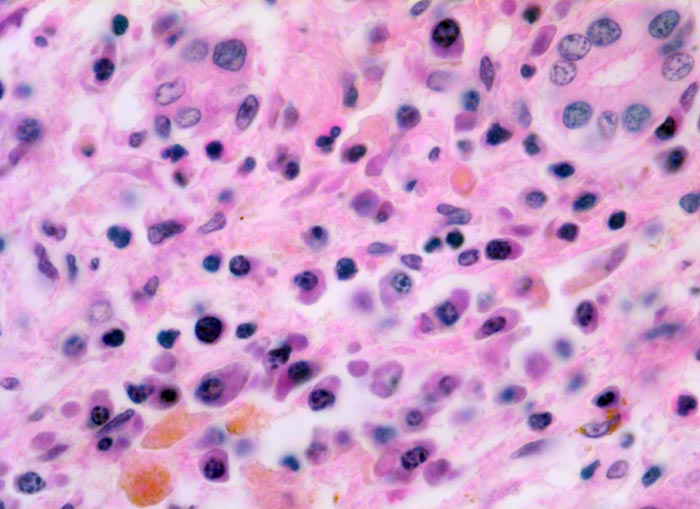

Das histologische Bild der akuten Hepatitis vom Virustyp ist gekennzeichnet durch eine lobuläre Entzündung bei fehlender portaler Fibrose und nur geringer entzündlicher Infiltration der Portalfelder. Es finden sich ballonierte Hepatozyten, Apoptosen (> 1164) und fleckige Nekrosen. Perivenuläre Nekrosen, Brückennekrosen oder konfluierende multilobuläre Nekrosen und eine läppchenzentrale Cholestase können vor allem in klinisch fulminant verlaufenden Fällen nachgewiesen werden. Zahlreiche Makrophagen, welche Diastase-PAS positives Zeroidpigment (> 4319) von phagozytierten nekrotischen Hepatozyten enthalten, zeugen im subakuten Stadium von einer abgelaufenen akuten Hepatitis mit Parenchymnekrosen. Eine Unterscheidung der verschiedenen Typen der viralen Hepatitis und einiger Formen medikamentöser Hepatitiden gelingt rein morphologisch aufgrund des unspezifischen Bildes meist nicht. Für eine ätiologische Klassifizierung sind zusätzliche klinische Angaben erforderlich (Anamnese, Medikamente, Serologie).

• Regelrechte Läppchenarchitektur.

• Lobuläre gemischte Entzündung.

• Ansammlungen zeroidbeladener Makrophagen innerhalb von Parenchymnekrosen (abgebaute fleckförmige Nekrose).

• Apoptosen (hypereosinophile abgerundete Leberzellen).

• Portale gemischte Entzündung.

• Fehlende Fibrose.